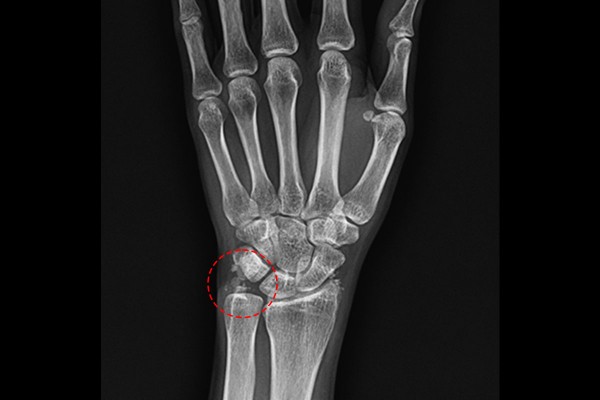

환자분 손목의 상태를 파악하기 위해 X-RAY 검사를 시행하였을 때, 석회가 확인되었습니다.